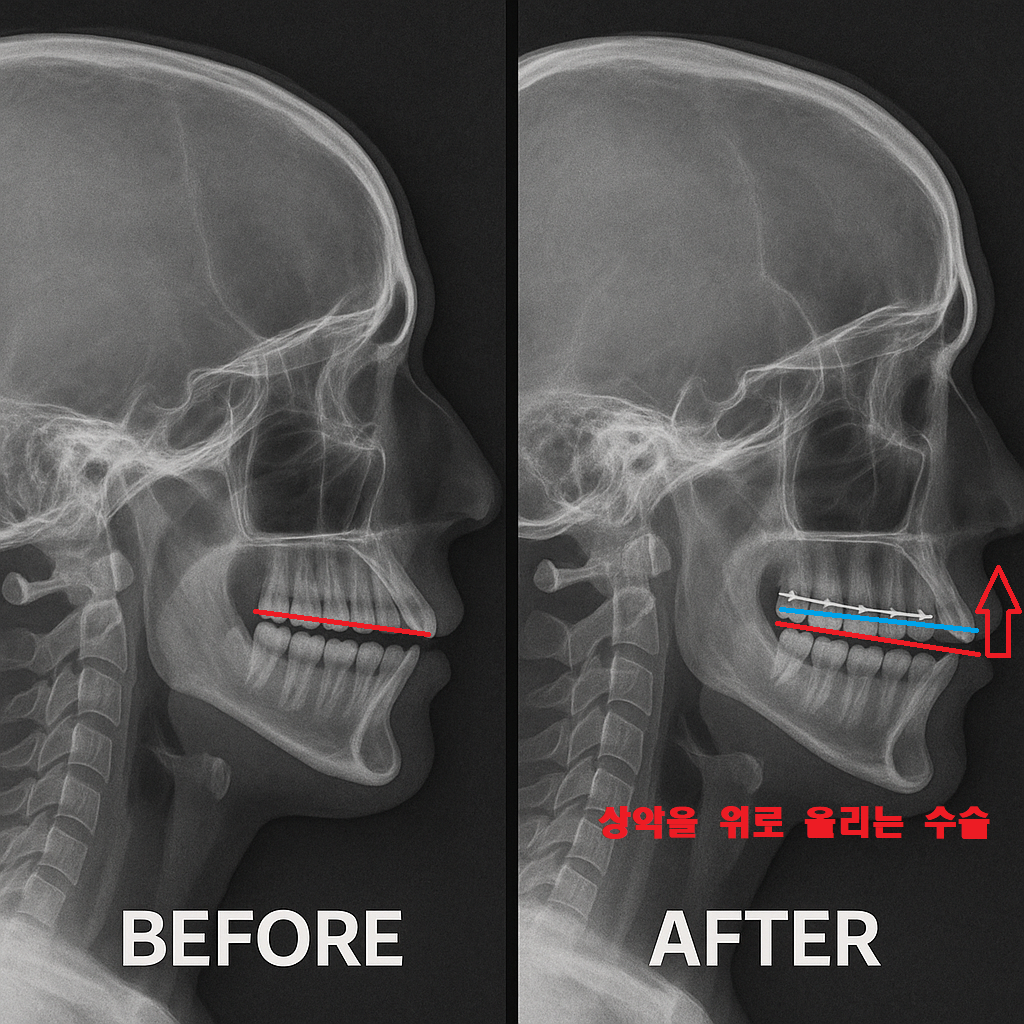

1.수직 과성장된 상악골의 절개-Le fort I수술(양약)

첫번째 상악골을 잘라버리는 수술 과정은 양악의 일종으로

과정성장된 상악골을 잘라서 수직으로 올리는 방법입니다

효과는 확실하지만 수술이라는 부담과

그리고 단순히 거미스마일을 개선하기 위해서

이런 양악수술을 선택하기에는 두려운게 현실입니다